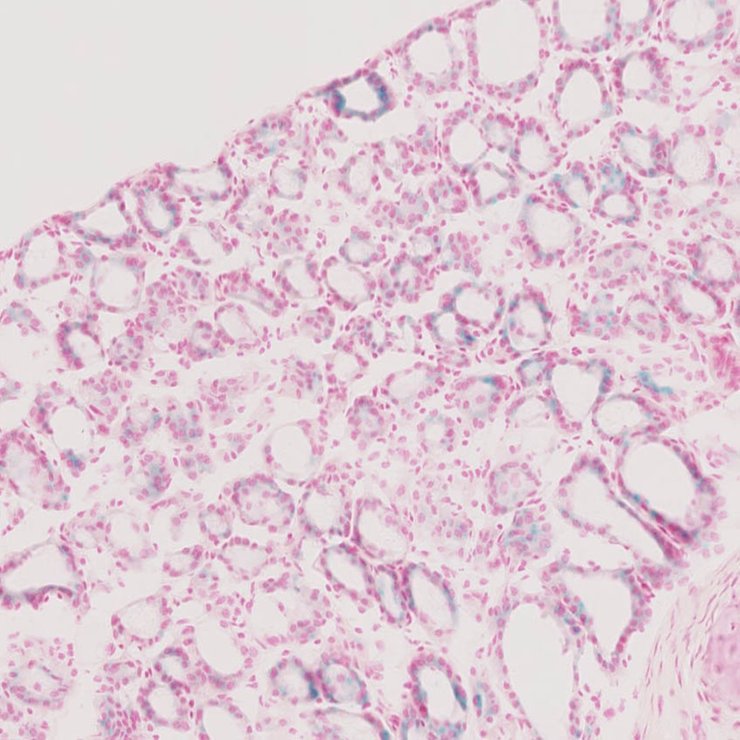

TS28: lung Present JAX_1804286

Specimen JAX_1804286: postnatal adult; Hctm1b(EUCOMM)Wtsi/Hc+ (more )

Structure Level Pattern Image Note